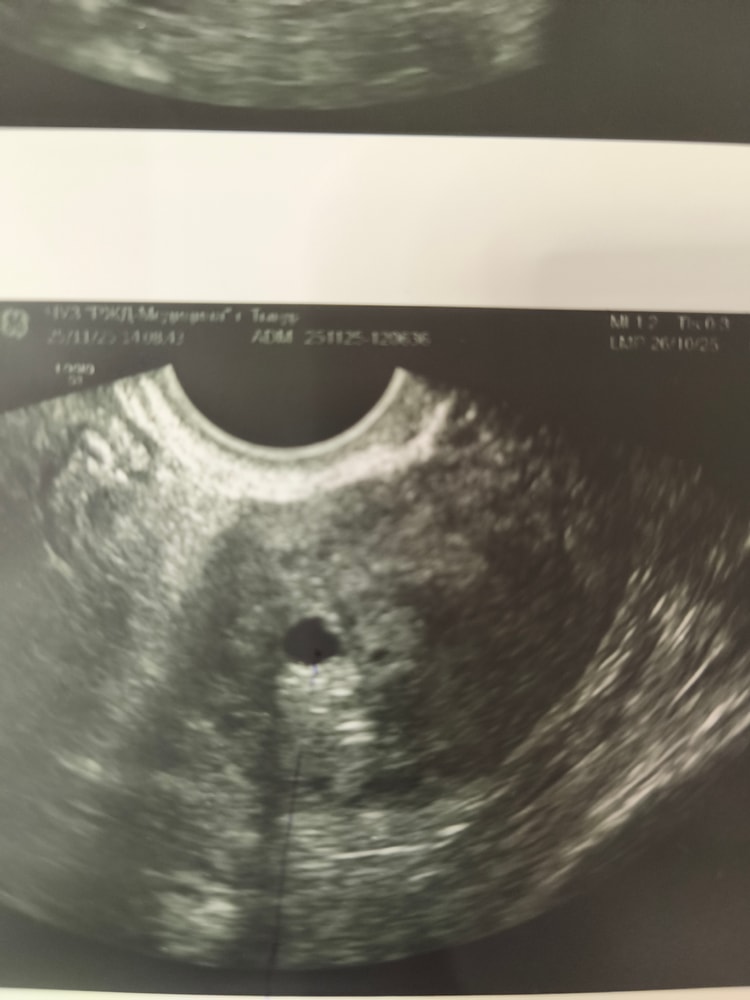

В первый день задержки якобы увидели пя, на узи пошла так как были бежевые выделения. В первый день задержки пя 4,5 мм, я очень сильно сомневаюсь что это было оно, так как овуляцию отслеживала по узи и была 10.11.25 а узи 24.11.25. Сегодня повторила через неделю, срок по месячным 5,2 н.пя 6,5мм деформация ,не выросло практически , отправляют на чистку нет желточного мешочка.Сравнивают с первым узи, но разные клиники. Прекреплю снимки. У меня аденомиоз. Могли первый раз перепутать, так они даже находятся в разных проекциях. Первый снимок в день задержки, ниже от сегодняшнего дня